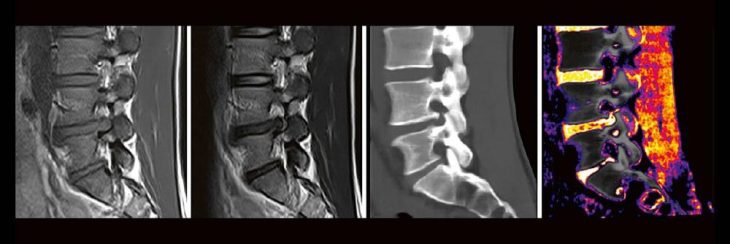

Professor Dr. med. Marc Brockmann WEITERENTWICKLUNGEN VON KOPF BIS FUSS BEIM VC Oberstarzt Dr. med. Stephan Waldeck DEEP-LEARNING-REKONSTRUKTION IN DER NEURORADIOLOGIE Die CT ist ein essentielles Routine-Verfahren in der Neuroradiologie. Bei steigender Bildqualität konnte die Röntgendosis mit neuen Technologien in der letzten Dekade deutlich gesenkt werden, was für die zielgerichtete und möglichst schonende Behandlung vonRead more about DEEP-Learning-Rekonstruktion in der Neuroradiologie (Webinar | Online)[…]